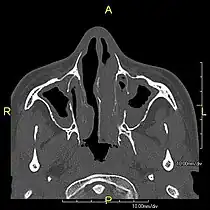

Axial CT image showing chronic sinusitis in an individual with Kartagener syndrome